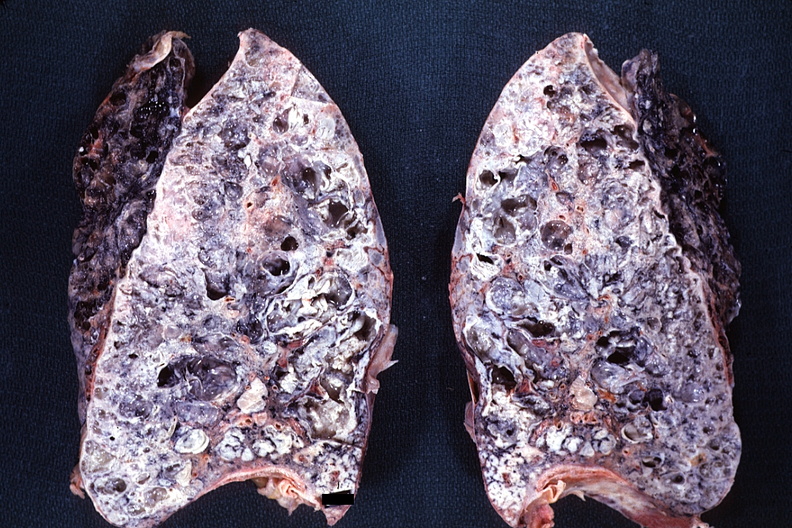

_原發性肺纖維化晚期

_重度肺纖維化的晚期

_重度肺纖維化晚期症狀